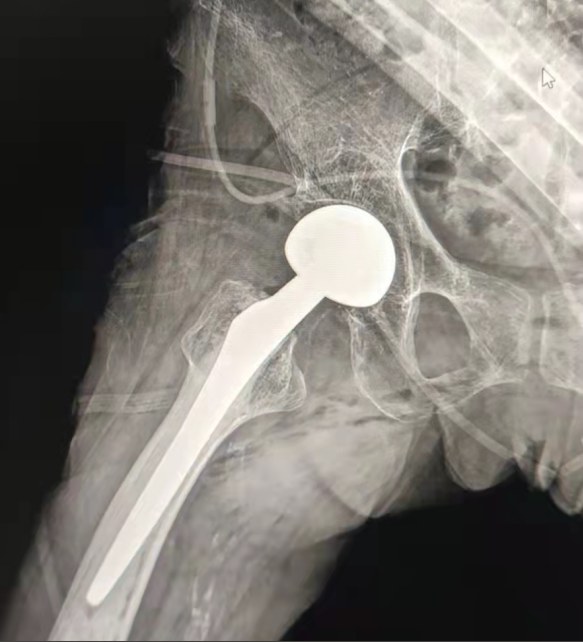

Case Sharing | Ein 70-jähriger Patient erhielt den gesamten Hüfte rsatz mit Lepu-Hüft system

Zementiertes Hüft system:

Co-Cr-Mo-Legierung materialien

Hohe Verschleiß festigkeit

Große mechanische Festigkeit

Schulter faden Design

Leicht installieren, halten und Winkel justieren

Polierte Oberflächen behandlung

Um ein aus gezeichnetes Knochen einwachsen zu erreichen Gewährleistung der Stabilität der frühen Fixierung

12/14 Standard-Verjüngung design

Proximal Mix Anatomy

Design-Kollektion Europa und USA Stem Features

Distal Beide Seiten Adge Cutting Behandlung

Reduzieren Sie den Druck in der Mark höhle